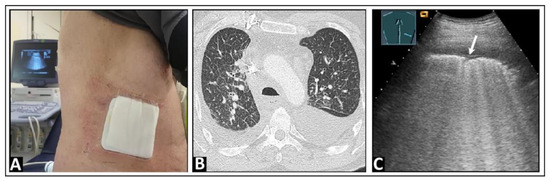

2. Basic Principles and Examination Technique